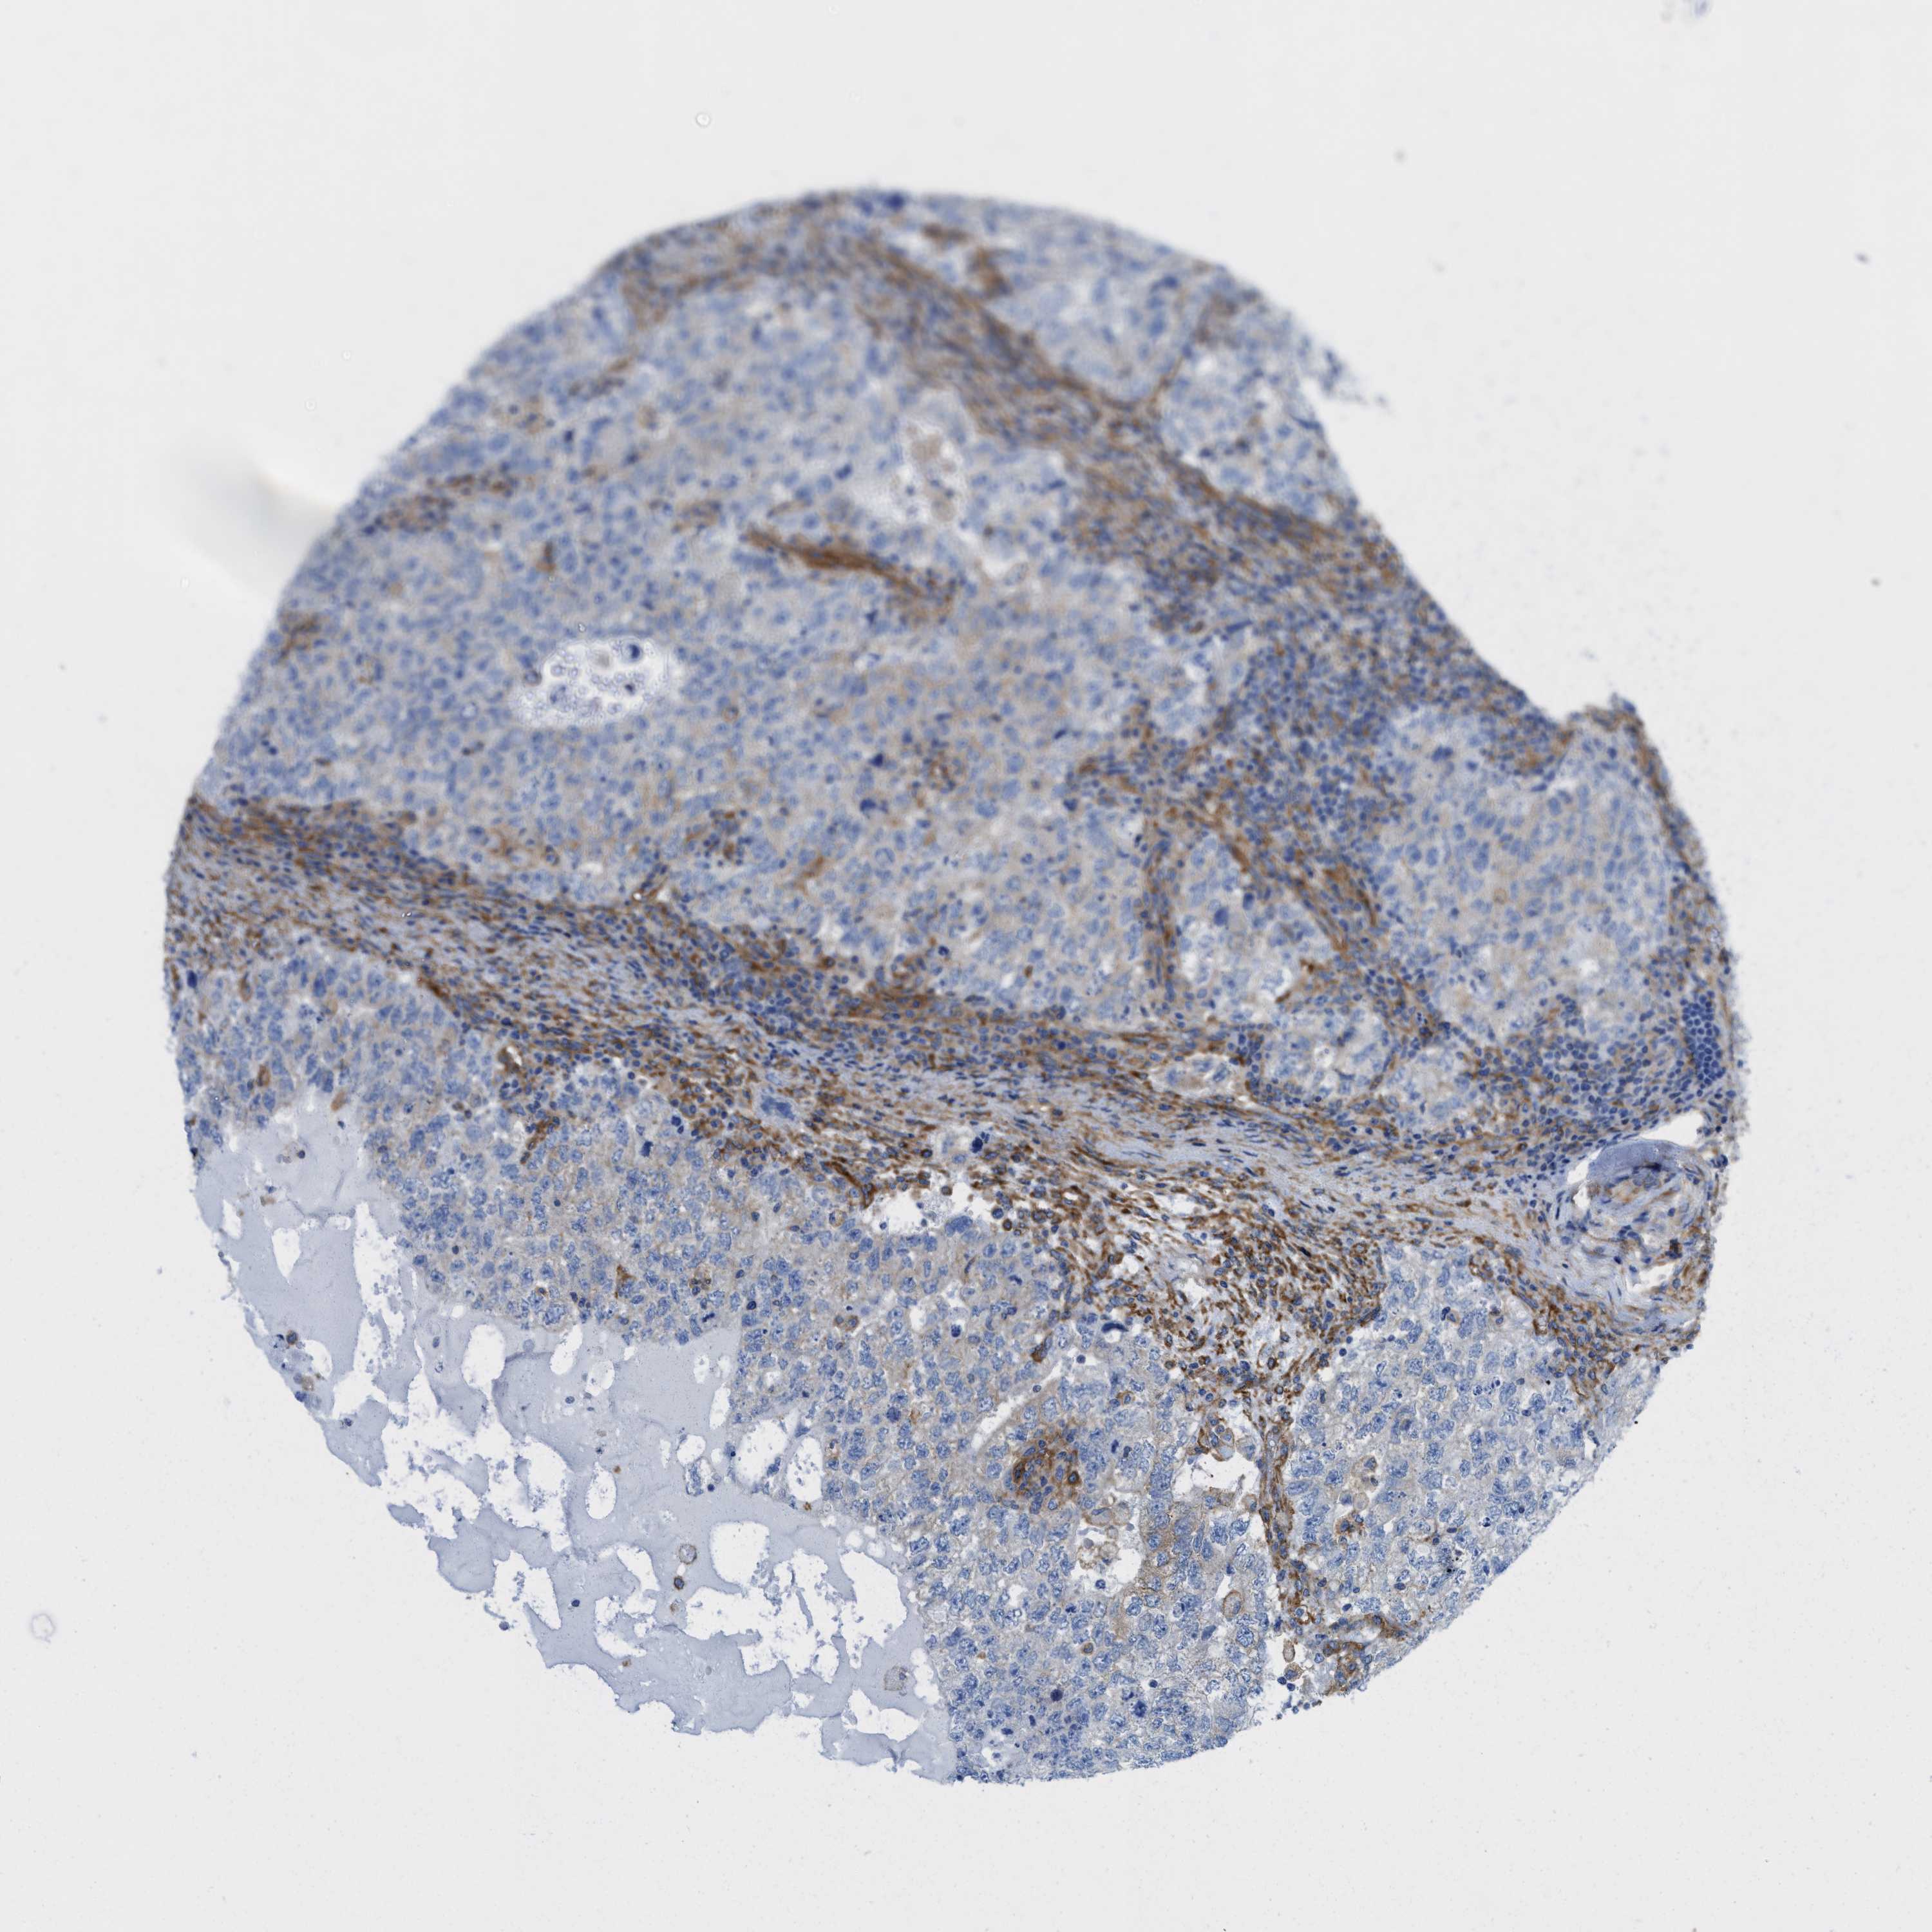

TESTIS CANCER - Protein expressioni

A mouse-over function shows sample information and annotation data. Click on an image to view it in a full screen mode. Samples can be filtered based on level of antibody staining by selecting one or several of the following categories: high, medium, low and not detected. The assay and annotation is described here.

Note that samples used for immunohistochemistry by the Human Protein Atlas do not correspond to samples in the TCGA dataset.

Antibody stainingi

Antibody staining in the annotated cell types in the current human tissue is reported as not detected, low, medium, or high, based on conventional immunohistochemistry profiling in selected tissues. This score is based on the combination of the staining intensity and fraction of stained cells.

Each image is clickable and will lead to virtual microscopy that enables deeper exploration of all samples and also displays staining intensity scores, fraction scores and subcellular localization as well as patient and tissue information for each sample.

Antibody CAB016402

Carcinoma, Embryonal, NOS

Seminoma, NOS